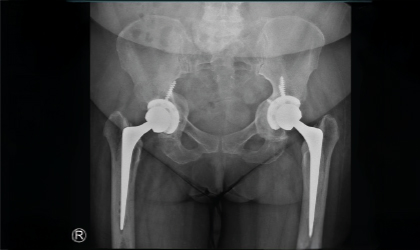

Revision Knee Surgery Case Study

Rheumatoid Arthritis, Conquered

This 54 year old professor from a medical college was referred to us with severe damage to both hips